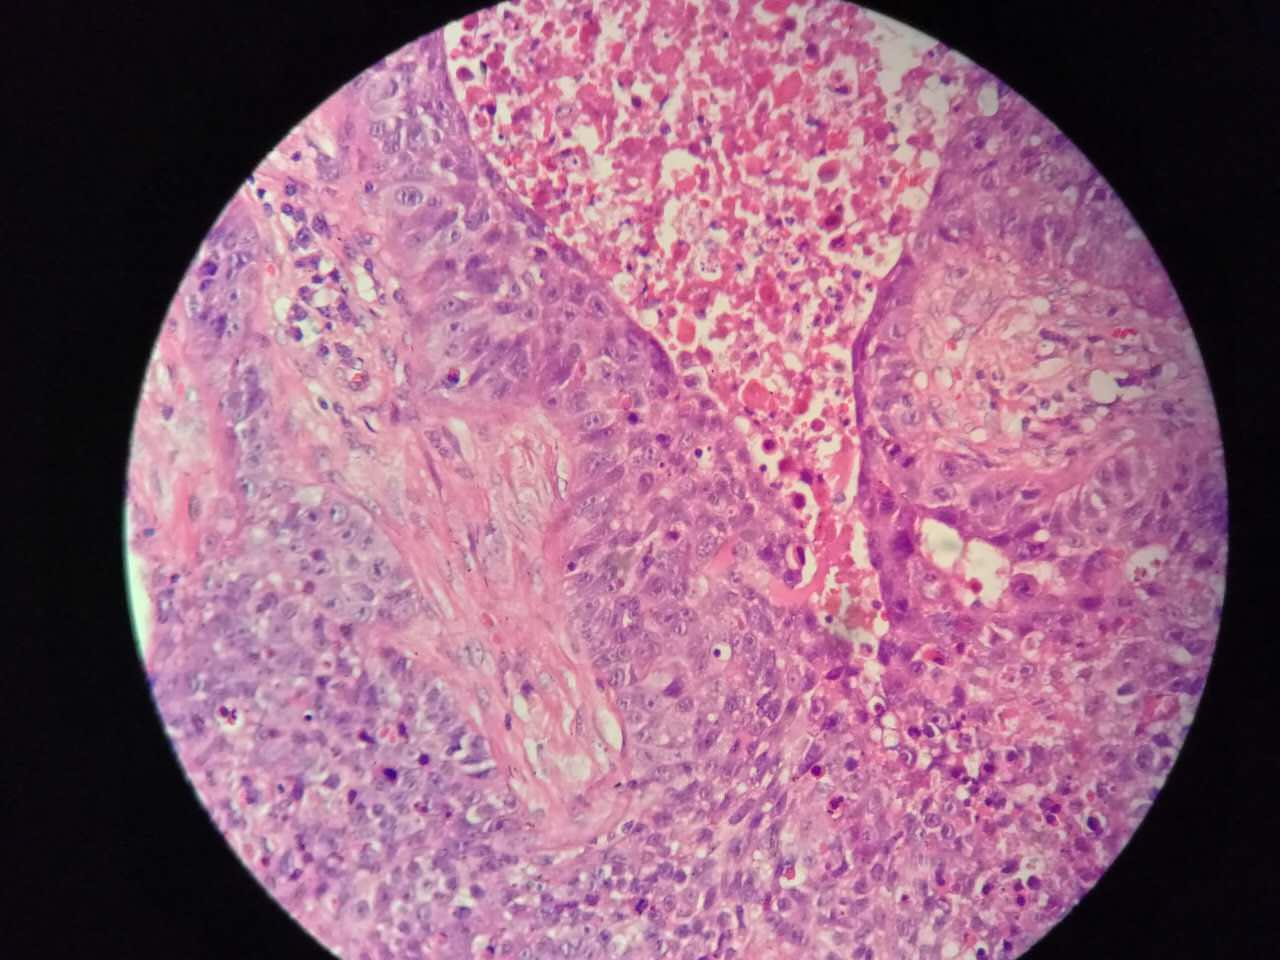

鳞癌

鳞癌生长,呈巢团状

巢团边界大多清楚

巢团可以很大,中央血供不足,就会坏死

中央红色的,有碎核

这个鳞癌不是早期

坏死也可以很大

较大的粉红区都是坏死,可以看出坏死是因为巢团大,中央坏死

左手边有一点鳞癌,右手边有正常肺泡组织,中间有坏死物,这是为什么呢?

坏死物质渗出。

并且可以有吞噬,坏死物里常有血液成分

肿瘤周围不应是缺血,坏死一般在巢团内